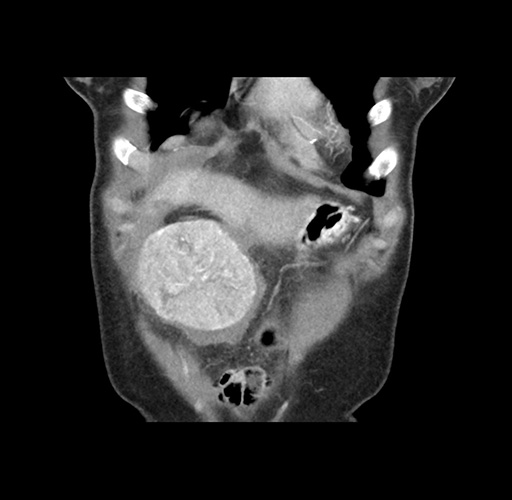

Imaging Analysis

Look through the patient's CT scan to identify any areas of concern for the necessary procedure.

Based on your CT findings, which issue(s) would give reason for "planned slowing down moment(s)" in this case?

Considering a standard left lateral sectionectomy procedure, what step(s) of the operation would you do differently in this case ?